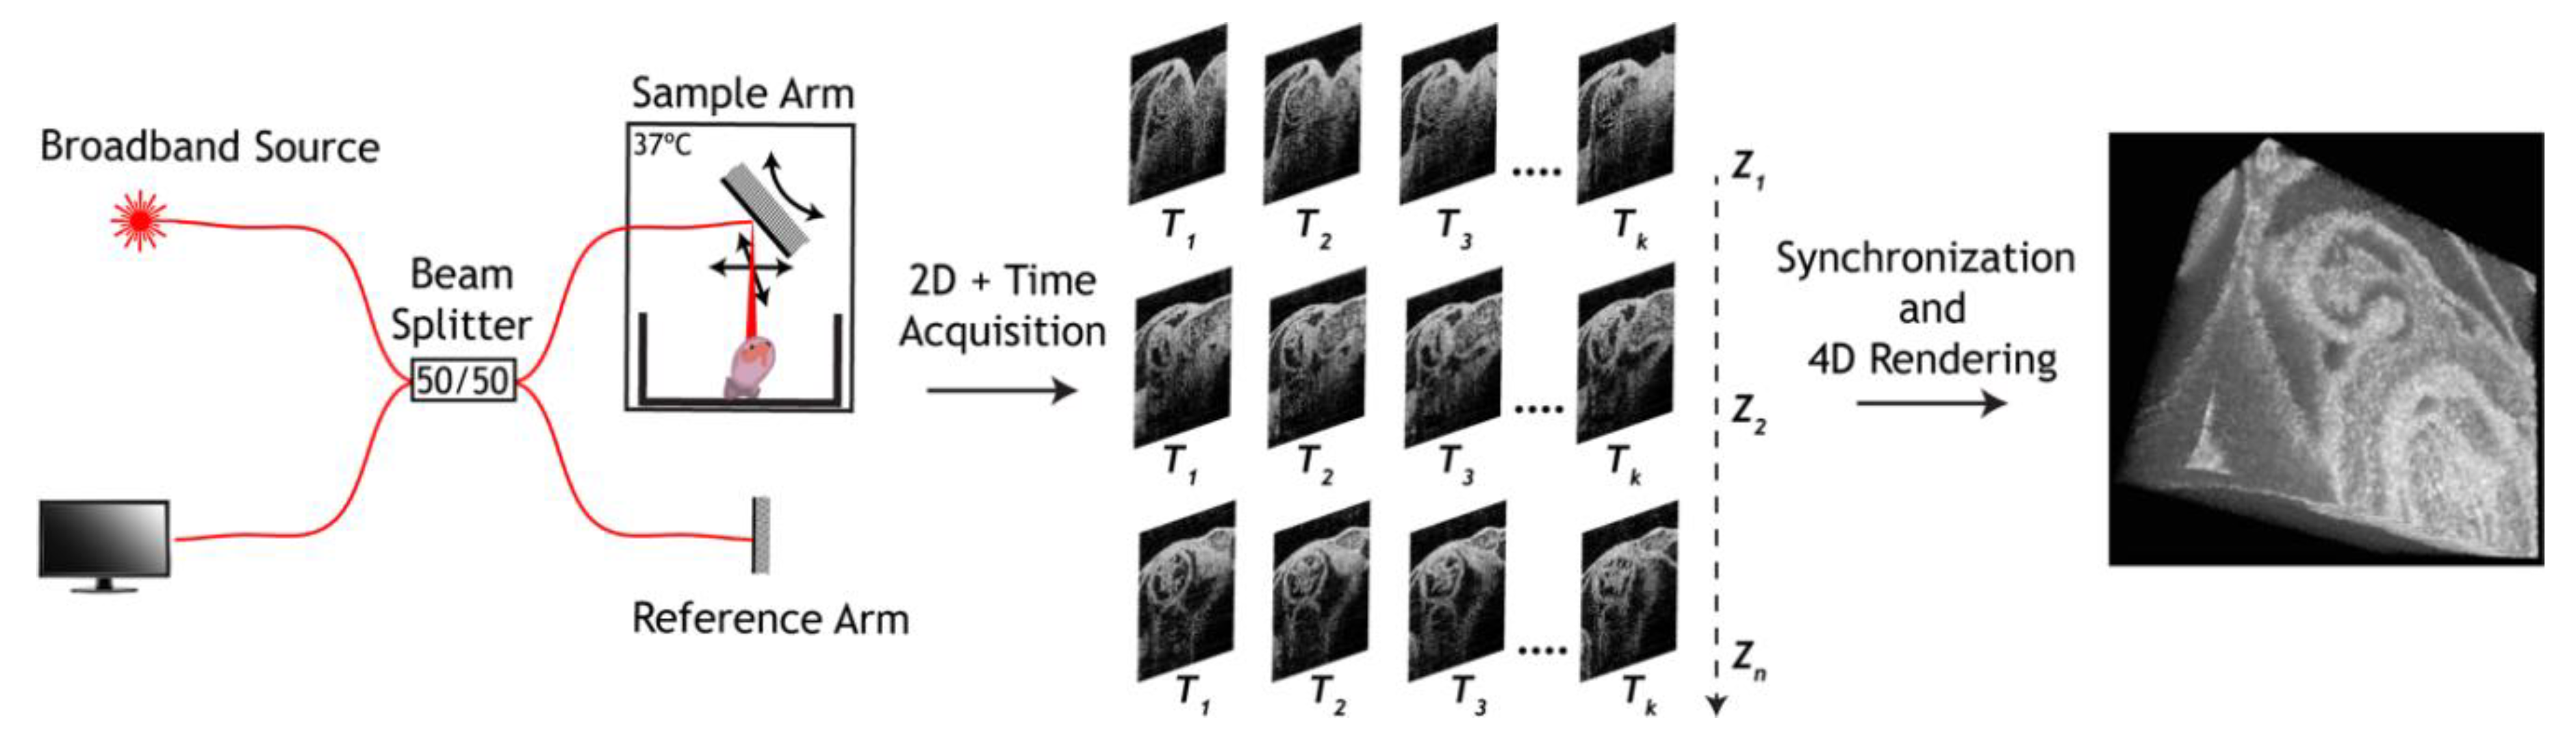

3. Approaches to Volumetric Cardiodynamic Imaging

- Larina, I.V.; Larin, K.V.; Dickinson, M.E.; Liebling, M. Sequential Turning Acquisition and Reconstruction (STAR) method for four-dimensional imaging of cyclically moving structures. Biomed. Opt. Express 2012, 3, 650–660. [Google Scholar] [CrossRef] [Green Version]